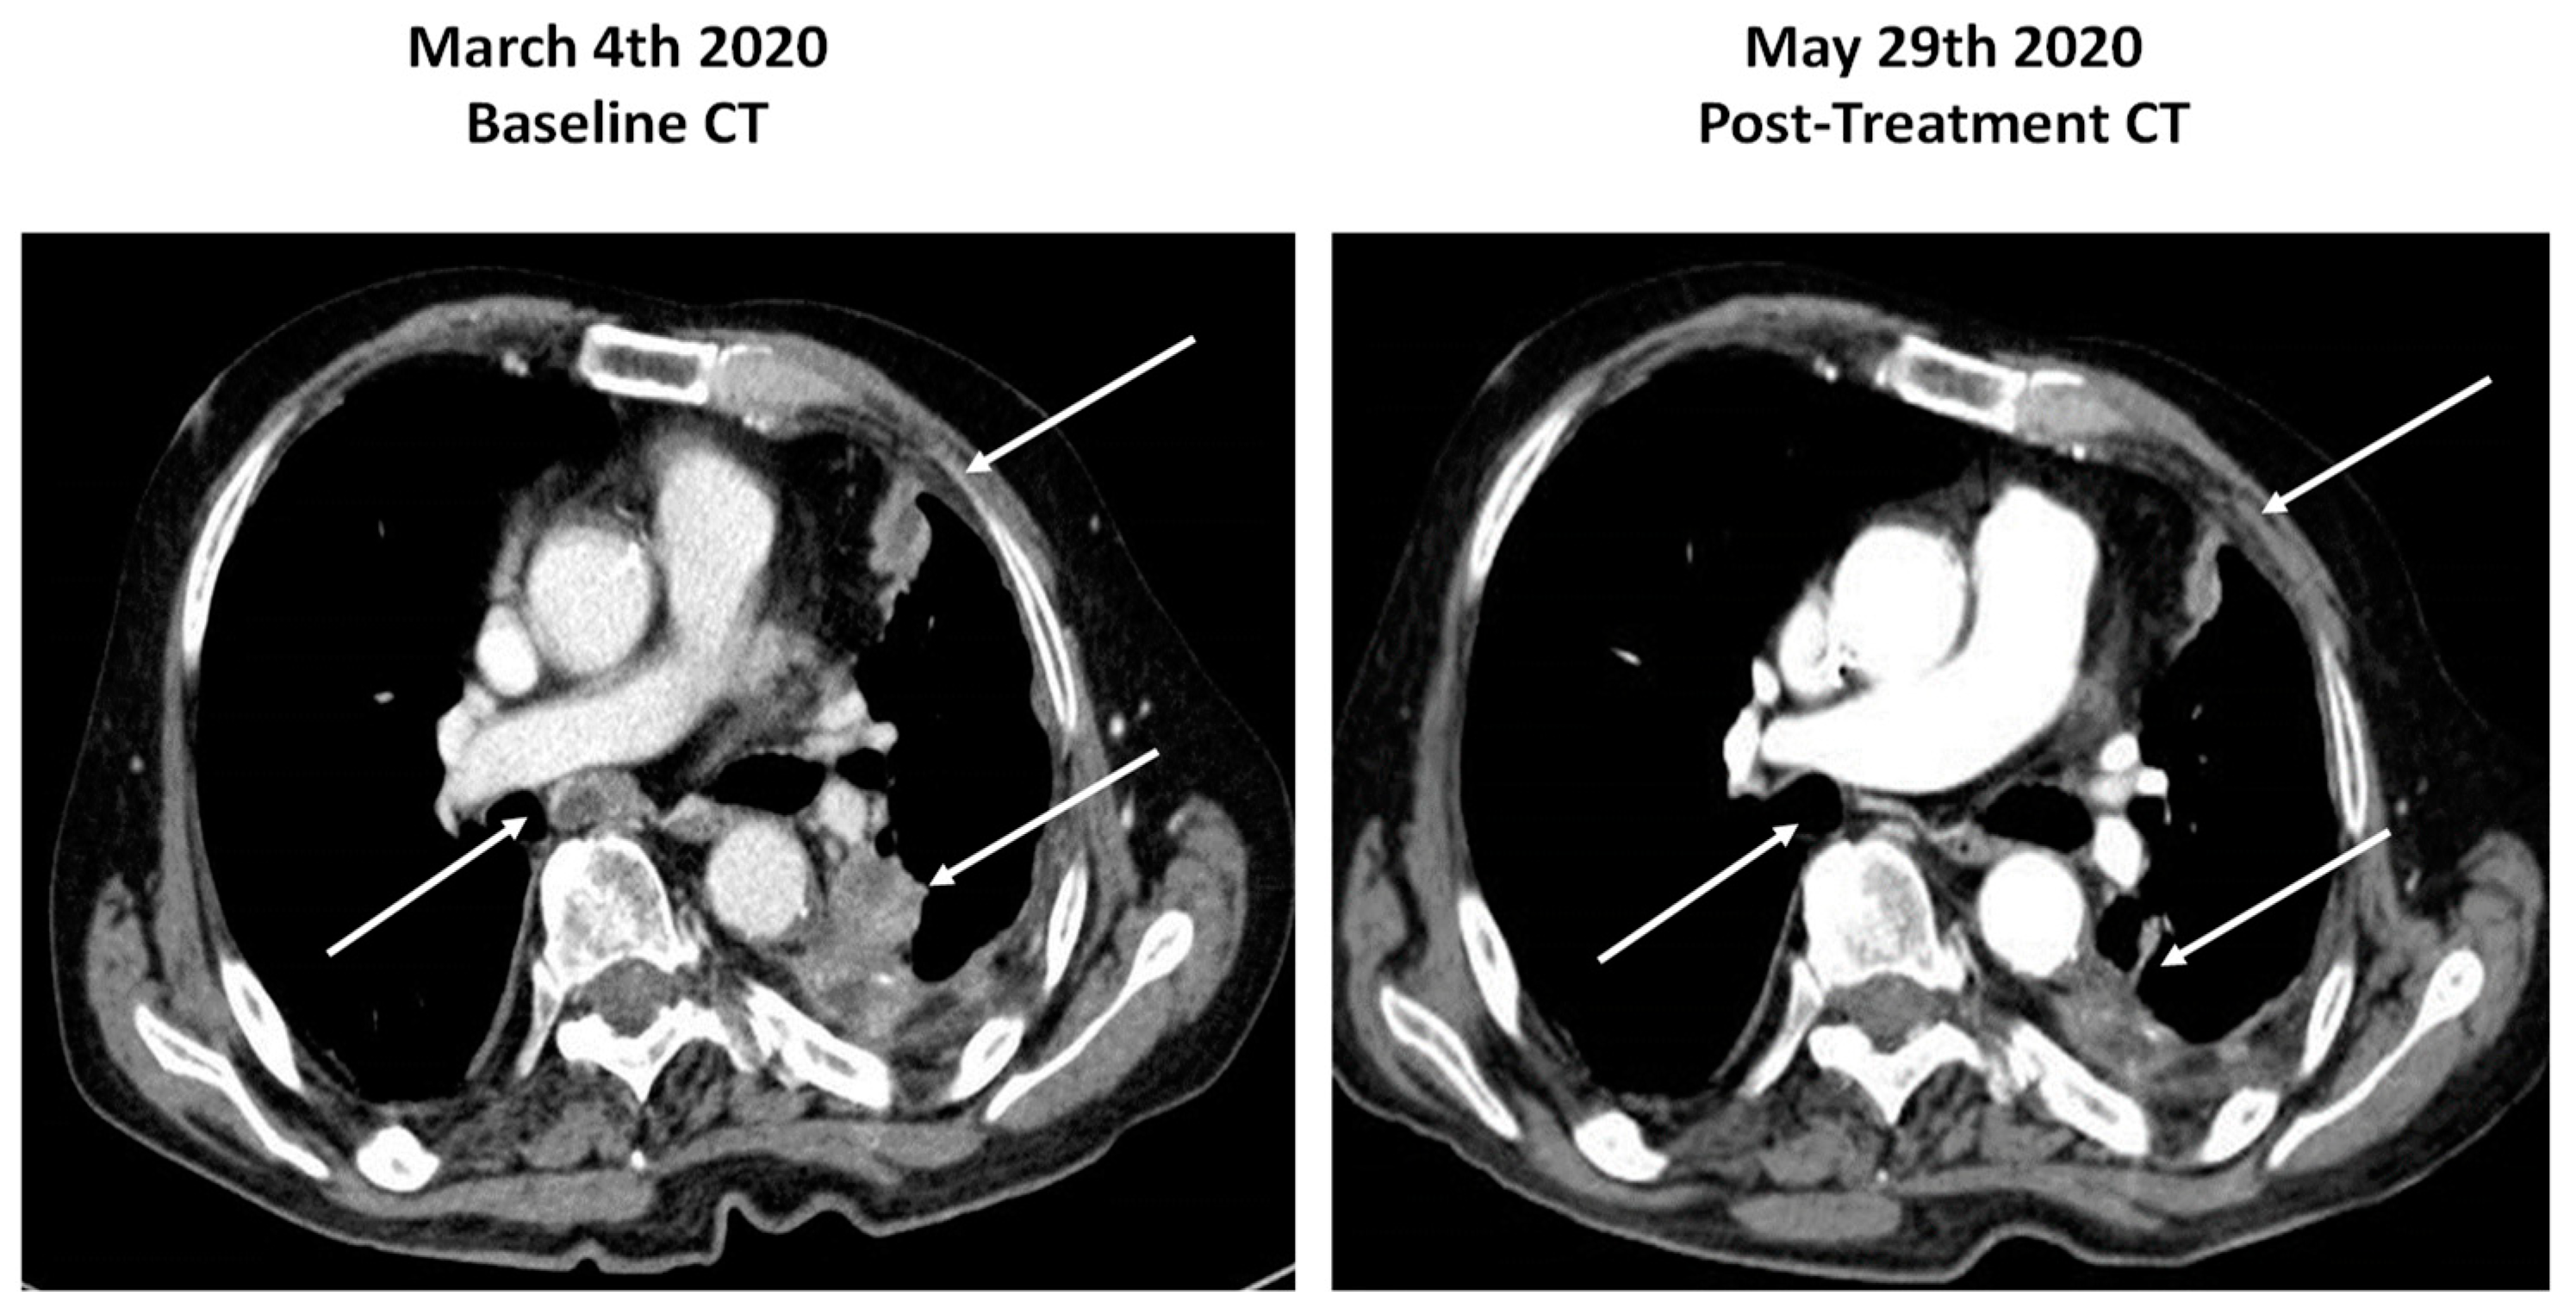

In May 2019, our patient was admitted to the emergency room for acute respiratory distress. A CT scan showed left pleural effusion, thickening, and nodules of the pleural surface, several mediastinal lymph node metastases, and a bone metastasis in the IX left rib (Figure 2 left). Pleural effusion cytology came back negative for malignancy. An ultrasound-guided bone biopsy of the lesion at the IX rib level was carried out. Histology revealed malignant cells with adenocarcinoma aggregation. The immunohistochemical workout was guided by the anamnesis of prostate cancer and included markers of prostatic differentiation (NKX3.1 and PSA) and markers of lung differentiation (TTF-1 and CK7). The cancer cells turned out to be highly immunoreactive for TTF-1 and BerEP4 and negative for the prostatic markers, leading to the diagnostic suspect of lung adenocarcinoma (Figure 1 top panel).

In January 2020, due to recurrent pleural effusion and respiratory failure, the patient was admitted to the thoracic surgery ward and a talc pleurodesis was performed. The CT scan showed a progressive disease with several pleural metastases and bone metastases of the IX and V left ribs with muscular infiltration, despite a PSA level of 1 ng/mL.

In February 2020, the patient underwent another CT-guided pleural biopsy with a histological diagnosis of a papillary poorly differentiated adenocarcinoma (still immunoreactive for TTF-1 and negative for NKX3.1, p40, chromogranin, and calretinin). Histology always excluded pleural mesothelioma. The histology report together with the lack of response to enzalutamide favored the diagnosis of peripheral NSCLC with pleural and rib infiltration, harboring the same TMPRSS2:ERG rearrangement found in the prostate cancer. The patient was therefore submitted to first-line chemotherapy with carboplatin and pemetrexed. In June 2020, after six cycles of chemotherapy, the clinical condition of the patient improved, and a control CT scan showed significant objective response of the pleural lesions (Figure 2 right).

Figure 2. CT scans of the lung lesions before and after chemotherapy with carboplatin and pemetrexed. Arrows highlight the significant response to therapy of mediastinal, pleural, and lung lesions.